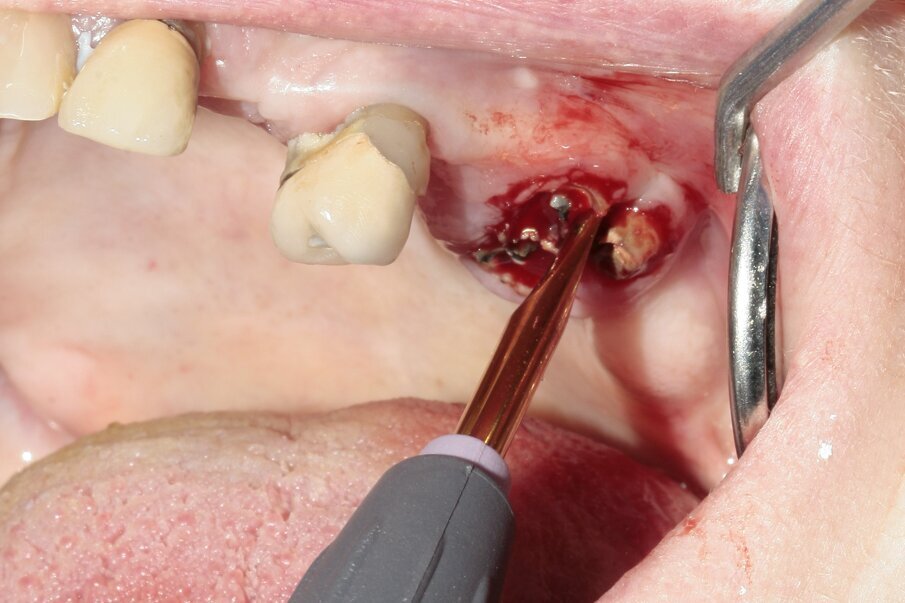

Fig. 6: Continued luxation with Luxator P1 (straight blade, dark green).

The new, very thin Luxator P-series periotome made it possible to perform an atraumatic extraction with minimal loss of bone. Luxator P4, with its extremely sharp dual-edge blade, was used, followed by Luxator P1, once some space was created. Although the blades of these sophisticated instruments are reinforced with a titanium coating, they should only be used to cut the periodontal ligament and never to elevate the tooth. After sectioning the tooth and gently cutting the periodontal ligament, each root could easily be taken out with the help of diamond tweezers.